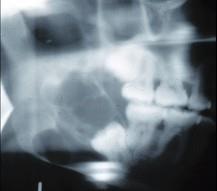

问题 女,32岁,右下后牙龈向外膨隆,后牙渐松动3个月。X线片(如图)示右下颌磨牙区颌骨呈蜂房样改变,病变区牙根呈锯齿状吸收。该病人最可能的诊断是 ( )

选项 A.右下颌骨骨肉瘤 B.右下颌骨角化囊肿 C.右下颌骨成釉细胞瘤 D.右下颌骨骨巨细胞瘤 E.右下颌骨中央性颌骨癌

答案 C